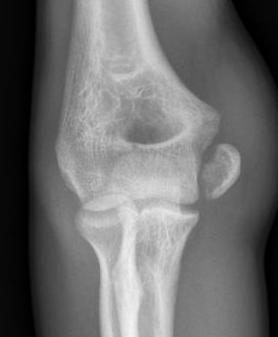

Displaced medial epicondyle fracture

Incarcerated medial epicondyle fracture

Clinical / Xray

- absent medial epicondyle on xray / compare to contralateral side

- non congruent joint reduction